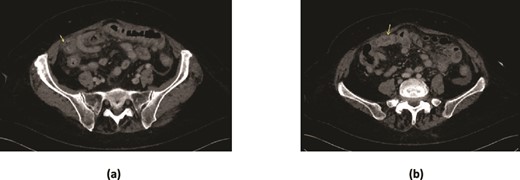

An 84-year-old lady presented with 1 day history of sudden onset severe generalized abdominal pain radiating to the back. This was associated with four vomits, and she had passed a small bowel motion earlier in the day. Her background history is significant for type 2 diabetes mellitus controlled with metformin. She did not have any previous abdominal surgeries, or gallstones. There was no family history of gastrointestinal diverticula, gallstones or malignancies. She resides at home, being the primary carer for her husband. On examination, she was febrile up to 38.2°C, blood pressure 150/69, heart rate of 90/minute, respiratory rate 18/minute and saturating at 95% on room air. Her abdomen was mildly distended, and generally tender with focal peritonism in the central abdomen. Her white cell count (WCC) was elevated at 12.0 × 109/L (reference: 4.0–11.0 × 109/L), neutrophils 10.50 × 109/L (reference: 2.0–7.50 × 109/L) and c reactive protein (CRP) of 40.0 (reference: 0.0–5.0). A computed tomography (CT) scan demonstrated marked mural thickening of the small bowel in the right lower abdomen with two areas of mural discontinuity suggestive of small bowel perforation. There was moderate ascites, without extraluminal gas or pneumatosis intestinalis. Distally, there was a non-specific ovoid soft tissue density structure in a small bowel loop, beyond which small bowel loops were collapsed (Fig. 1). There was intrahepatic (up to 7 mm) and extrahepatic (13 mm) biliary tree dilatation without pneumobilia. The gallbladder had fundal mural thickening, without features of cholecystitis. There was no CT evidence of a biliary-enteric fistula. She underwent an urgent laparotomy which demonstrated four quadrant peritonitis, and two separate areas of necrotic mid small bowel, jejunal diverticula with perforations at the mesenteric border. There was a palpable 3 cm solid intraluminal mass distal to the perforations in the proximal ileum, significant proximal small bowel dilatation and multiple other uncomplicated jejunal diverticula (Fig. 2). There were no other luminal masses during a small bowel run. One hundred centimetres of small bowel was resected, and a side-to-side functional end to end small bowel anastomosis was performed 30 cm distal to the duodenojejunal flexure to 120 cm proximal from the ileo-caecal valve using a GIA 80 mm blue reload stapler. Histopathology demonstrated perforated necrotic small bowel diverticulitis without malignancy, with the palpable intraluminal mass confirmed as cholelithiasis. The patient had an uncomplicated recovery but due to deconditioning, was referred for inpatient rehabilitation after two weeks. At her 6 weeks follow-up, she reported no recurrent symptoms.

CT scan demonstrating (a) marked mural thickening of the small bowel in the right lower quadrant with areas of mural discontinuity (arrow) and peritoneal free fluid suggestive of perforation (b) ovoid soft tissue density in a small bowel loop, with collapsed small bowel loops distally.

CT has a high sensitivity (93%) and specificity (100%) in diagnosing gallstone ileus [5]. In the presented case, the CT highlighted marked mural thickening of small bowel and an ovoid structure with collapsed small bowel loops distally without evidence of pneumobilia (Fig. 1). The classic radiologic sign of gallstone ileus ‘Rigler triad’ includes presence of pneumobilia, intestinal obstruction and an ectopic gallstone [2]. In hindsight, our patient had two out of three of Rigler triad. Perforation secondary to gallstone ileus is very rare, with a review of 458 cases of gallstone ileus reporting only two cases of jejunal perforation [8]. Perforation often occured at the site of impaction, or previous sites of obstruction due to pressure necrosis of the jejunal wall from the gallstone [6, 7].